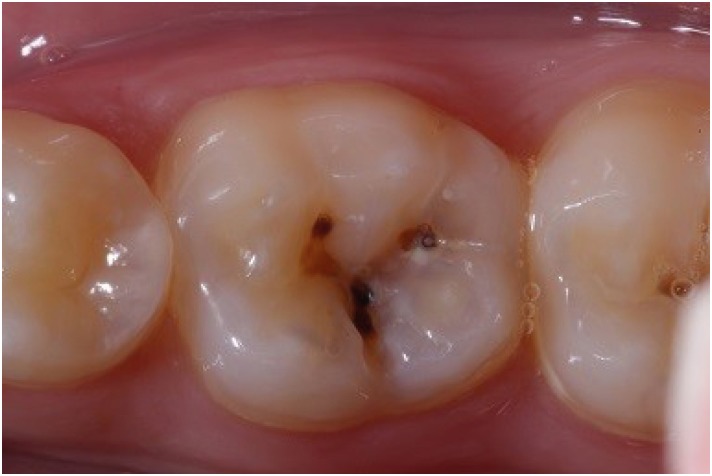

Initially, the verification of occlusal contacts was performed, as well as prophylaxis with pumice stone and water, at low rotation with Robbinson brush (Microdont, Sao Paulo, SP, Brazil). The enamel was accessed with a high-speed 1011 spherical diamond bur (KG Sorensen, São Paulo, SP, Brazil) and the carious tissue was removed with a low-speed #4 (KG Sorensen) spherical carbide bur (Figure 3). Continuing with the restorative process, etching was performed with 37% phosphoric acid (Condac – FGM, Joinville, SC, Brazil) for 30 seconds in enamel and 15 seconds in dentin followed by cleaning with water for double the time. The dentin was dried with sterile absorbent paper, and the application and photopolymerization of the adhesive system were done (Single Bond; 3M ESPE, Campinas, SP, Brazil) using LED light (Radii-Cal; SDI, Victoria, Australia). The acrylic resin matrix was removed from the recipient with water and dried with sterile gauze and air blast. A single increment of bulk-fill resin composite (Aura Bulk Fill; SDI) was placed in the cavity with a resin spatula, and the matrix was positioned on the tooth with light pressure, followed by a 20-second polymerization with and without the matrix (Figures 4, 5 and 6). After assessing the occlusal contact, the excesses were removed with finishing points and burs. Twenty-four hours after completing the restoration, it was finished and polished with rubbers Optimize (TDV, Pomerode, SC, Brazil) (Figure 7).

Figure 3

Class I cavity prepared with spherical bur.

rde-45-e9-g003.jpg